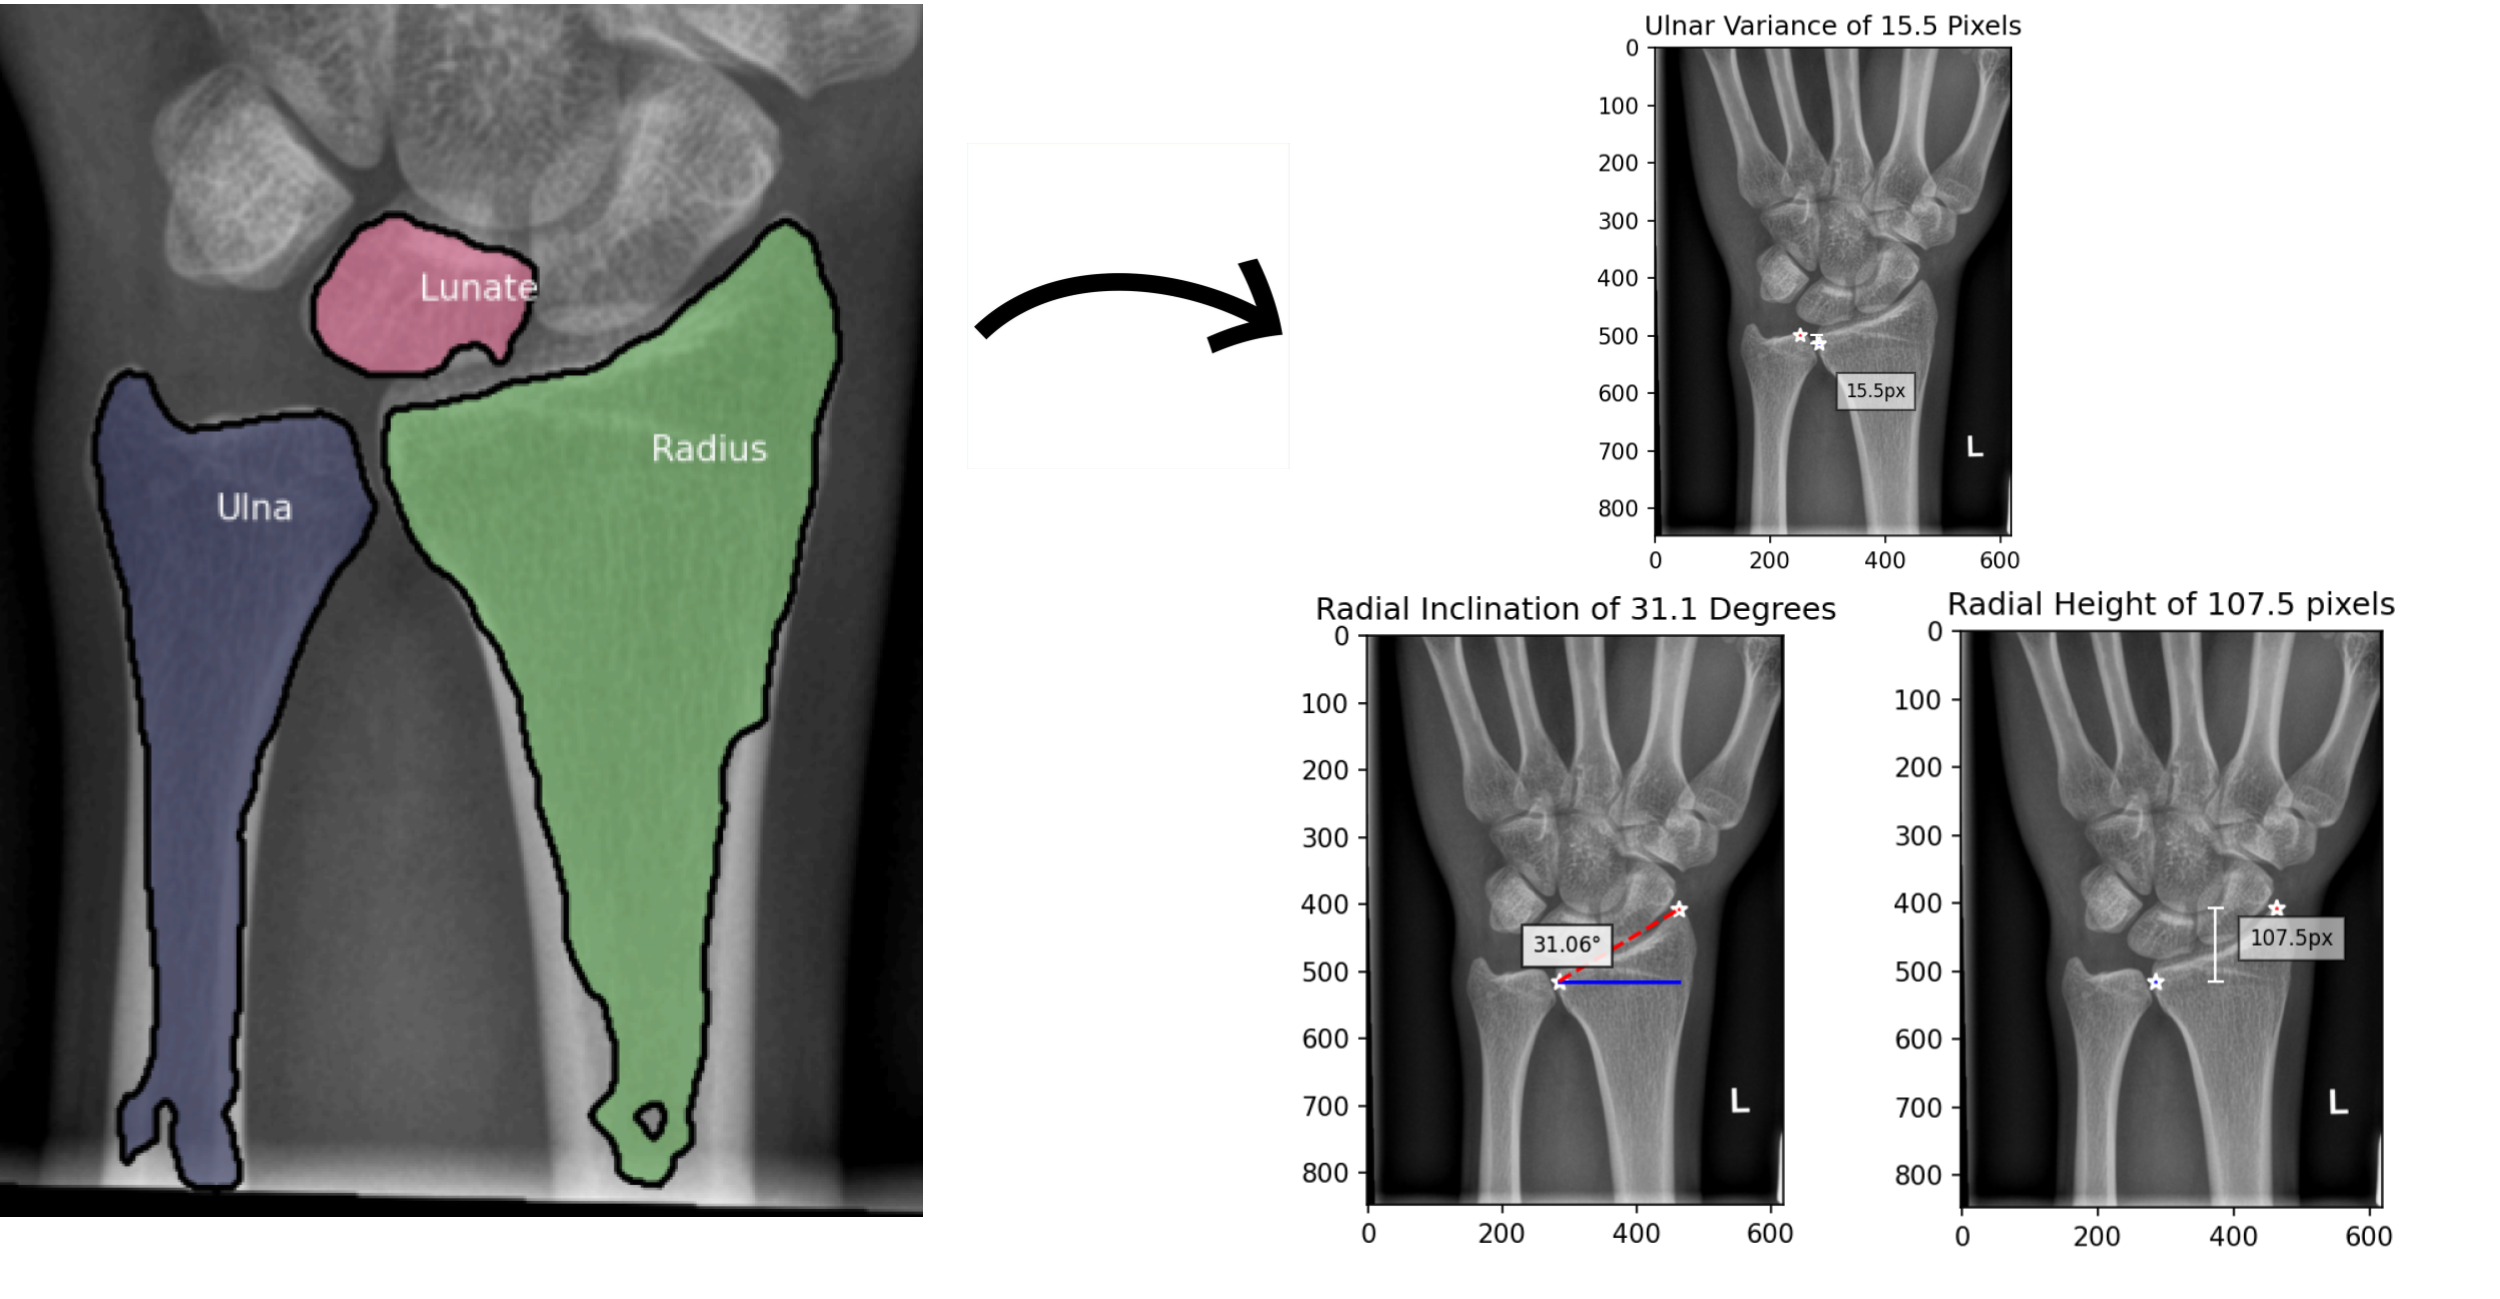

Automated Generation Of Angle and Height Measures in Distal Radius Fracture Recovery Prediction.

Onat Ozer and Thomas Talavage